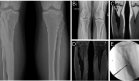

El paciente fue manejado inicialmente con antibioticoterapia intravenosa de amplio espectro (cefoperazona 2 g cada 12 horas) y rehidratación agresiva. Una vez estabilizado, se realizó colangiopancreatografía retrógrada endoscópica (CPRE) que confirmó estenosis de la vía biliar distal, procediéndose a colocación de prótesis biliar.

Posteriormente requirió intervención quirúrgica mediante coledocoyeyunostomía en Y de Roux combinada con pancreaticoyeyunostomía lateral debido a la enfermedad pancreática crónica avanzada.